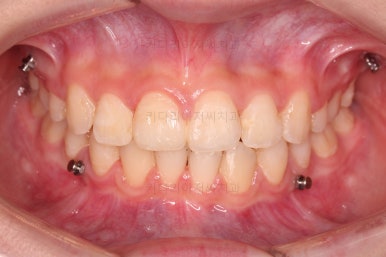

초진 시 입안의 모습입니다.

위아랫니가 많이 삐뚤진 않는데 뭔가 이상하죠?

어금니 맞물림은 지그재그로 잘 맞물려 있는데 위아래 앞니는 서로 앞뒤로 매우 멀죠.

비밀은 매우 자연스러워 보이지만 아래 앞니 2개가 선천 결손인 상태였습니다.

그래서 마치 단추 갯수와 단추구멍 갯수가 맞지 않아 단추가 남아버린 상황과 같았습니다.

앞니가 매우 튀어나와 보이고요.

당연히 앞니 기능은 못하게 됩니다.

앞니끼리 맞물리지 않다보니 아래 앞니는 점점 솟구쳐 과개교합(깊게 맞물려 아래 앞니가 거의 보이지 않는 현상)이 되게 됩니다.